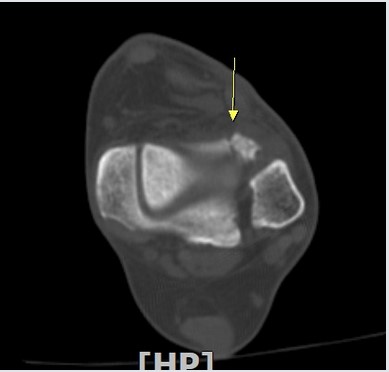

¾Õ°æ°ñºñ°ñÀδë Á¾´Ü¸é°Ë»ç¿¡¼­ °æ°ñºñ°ñÀδëÀÇ  Àú¿¡ÄÚ  ºÎÁ¾ ¹× ÀδëºÎÂøºÎ °æ°ñÀÇ

°ß¿­°ñÀýÀÌ  °üÂûµÊ(»çÁø 2, 3, 4)